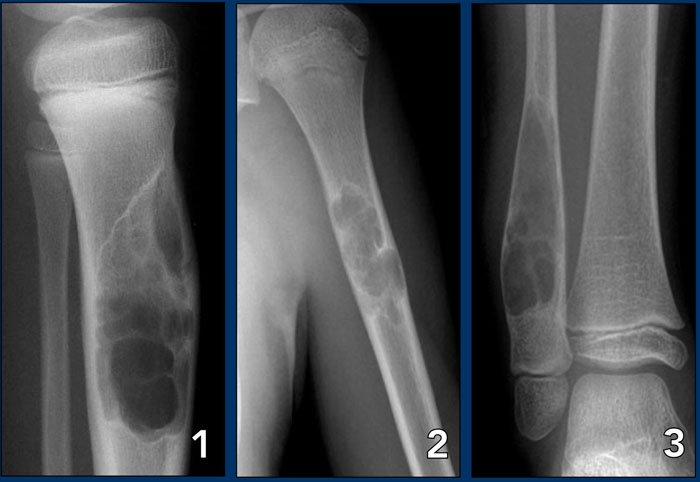

On the left three bone lesions with a narrow zone of transition.

Based on the morphology and the age of the patients, these lesions are benign.

Notice that in all three patients, the growth plates have not yet closed.

Images

1. Non-ossifying fibroma

2. Solitary bone cyst

3. Aneurysmal bone cyst